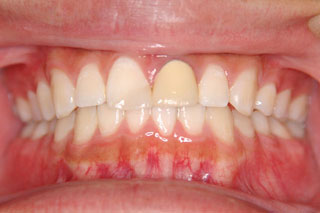

2年半ほどの治療で、装置を撤去し保定治療に移行しています。飛び出ていた前歯も、下の歯と正しく噛めるようになりました。口元の突出も消え、口唇閉鎖時に前歯が覗いて見えるという事も無くなりました。